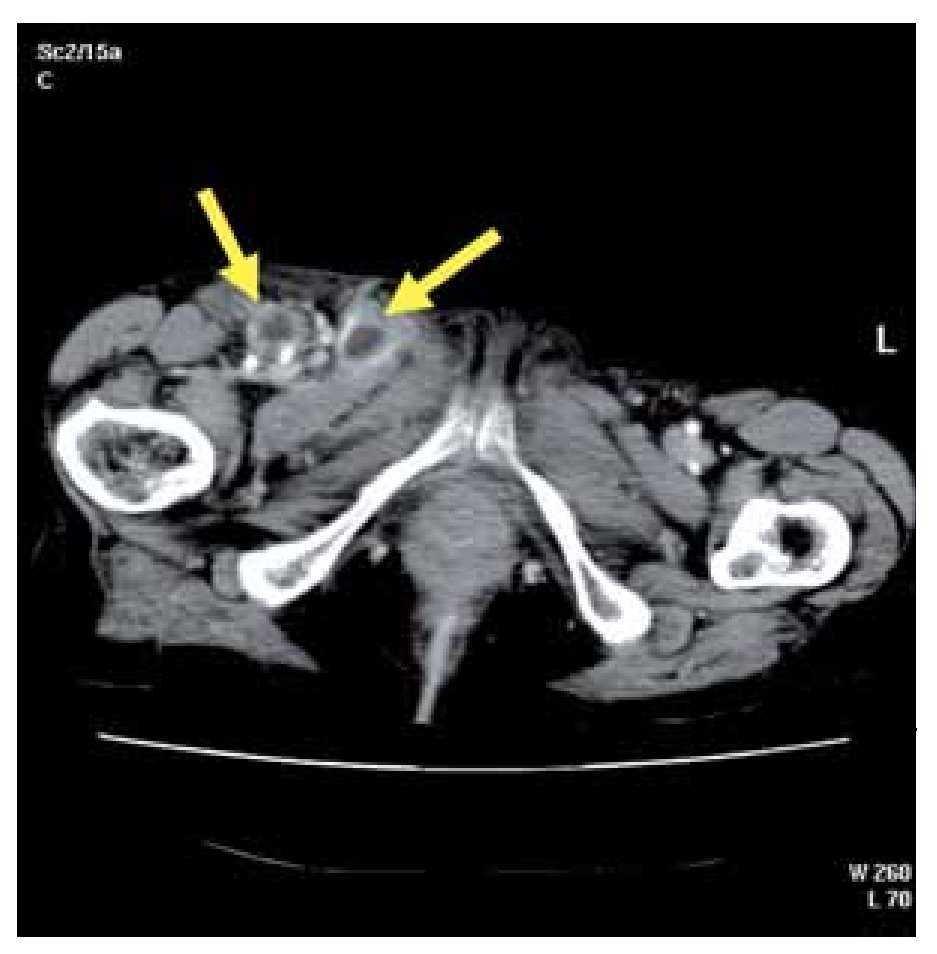

An 82-year-old female was admitted to hospital with seven-day history of right inguinal pain. The patient also complained of fever and malaise. There were no other associated symptoms and she denied a previous trauma. On physical examination she was febrile but other vital signs were normal. The chest exam revealed clear lungs with normal heart sounds and her abdomen was soft with normal bowel sounds. Only mild tenderness in the right flank was present. Her right leg was markedly swollen, indurated and with a descending erythema from her groin and proximal third of the tight to her knee. She had a painful and fluctuant area in her right groin and she also had physical signs of psoas inflammation. Laboratory studies showed leukocytosis with neutrophilia and D-dimer elevation. Deep venous thrombosis was initially suspected, so patient underwent Doppler ultrasonography. As this study did not show any alteration, a computed tomography (CT) was performed to investigate an infectious origin. The CT of the abdomen and pelvis revealed a right iliopsoas abscess affecting obturator (Figure 1) and adductors muscles reaching the distal third of the thigh adjacent to her knee. Multiple inguinal necrotic lymph nodes were also present (Figure 2). As a gastrointestinal infectious focus was suspected a diagnostic laparoscopy was decided, but there were no findings at surgery. Surgical drainage through right groin was made and purulent material was taken for culture. Intravenous empirical antibiotics were also administrated. Further diagnostic methods were made to elucidate the origin of this process when cultures of the purulent fluid yielded Pasteurella multocida. A new anamnesis revealed that the patient had a domestic cat and finally she remembered getting scratched on her right leg a few weeks ago. Detailed physical examination also demonstrated this little scratch, which probably was the primary source of infection. After surgical drainage and antibiotic therapy clinical course remained uneventful.

¿ Figure 1. Right iliopsoas abscess affecting obturator and adductors muscles.